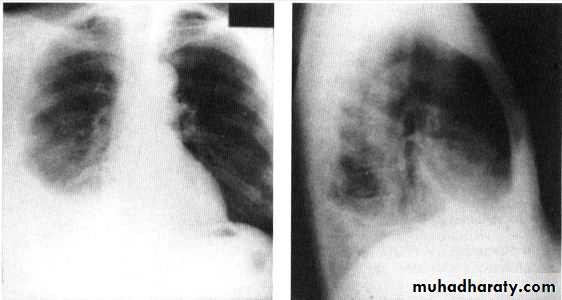

Chest X ray: The pleural fluid accumulates in the most dependent part of the thoracic cavity

The normally sharp posterior costophrenic angle is obliterated.

Upper surface is meniscus-shaped (meniscus sign).

Around 200 mL of fluid is required in order for it to be detectable

on a PA chest X-ray

The amount of pleural effusion may be small, large or massive.